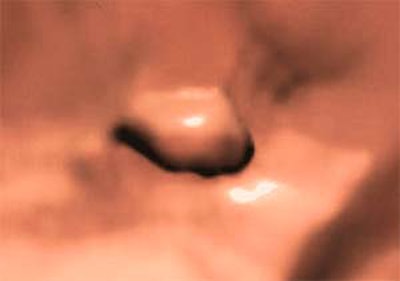

Polypoid artifacts related to partial-volume effects are a more serious shortcoming of the primary 3-D read, according to the group. Such artifacts tend to occur where air-fluid levels interface with the colon wall, especially when a meniscus effect is also present, the group wrote. Air-fluid haustral-fold interfaces are another characteristic location of polypoid artifacts, making evaluation of the uncleansed 2-D images vital for accurate interpretation. Since these artifacts result from the cleansing process, they are often present on the electronically cleansed 2-D images as well.

"Last of all, trapped air bubbles in an otherwise fluid-filled lumen can also give rise to convincing pseudopolyps on 3-D images," they wrote. "In such cases, the uncleansed 2-D images yield a rapid explanation."

| Above, pseudopolyp due to partial-volume effect at air-fluid wall interface in average-risk 54-year-old man undergoing virtual colonoscopy screening. Three-dimensional endoluminal image obtained with electronic cleansing shows 6-mm sessile lesion. (Images and caption used with permission of the American Roentgen Ray Society from AJR, © September 2003, Vol. 181:3, pp. 799-805. |